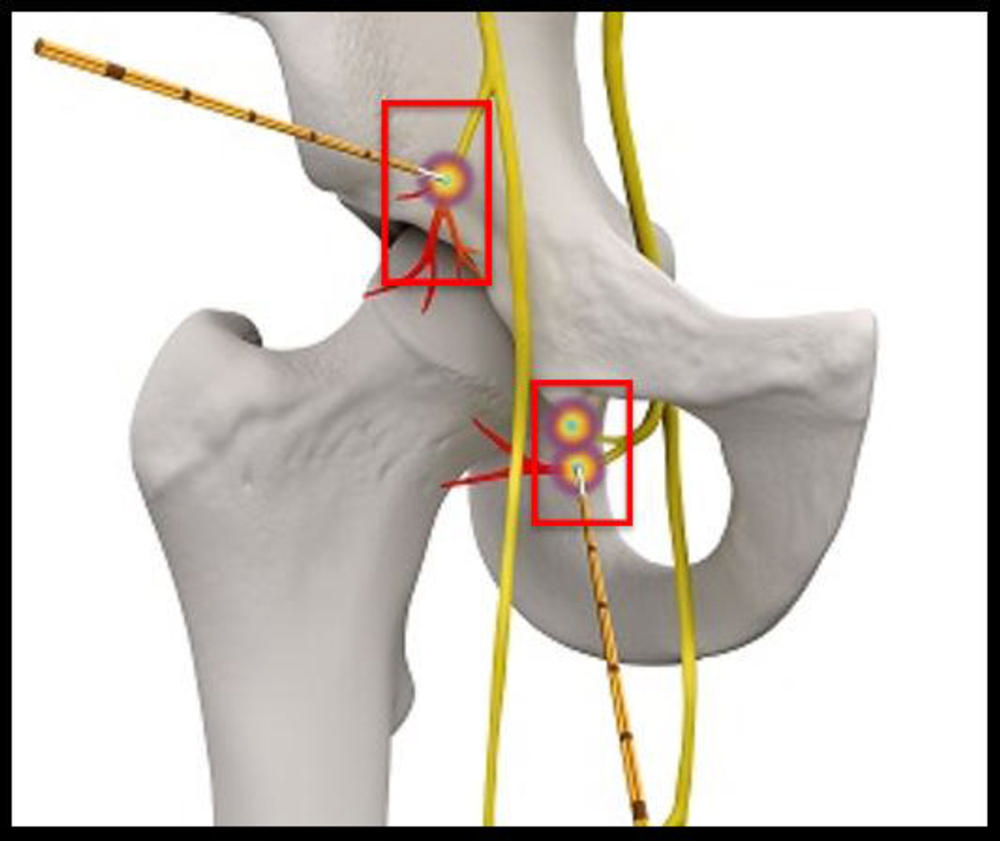

Dr. Gonzalez and colleagues have been studying the application of a novel interventional radiology treatment known as cooled radiofrequency ablation (c-RFA) to achieve pain relief in the setting of advanced degenerative arthritis. The procedure involves the placement of needles where the main sensory nerves exist around the shoulder and hip joints. The nerves are then treated with a low-grade current known as radiofrequency that “stuns” them, slowing the transmission of pain to the brain.

Figure 12. Hip-specific cooled radiofrequency ablation technique: There are three ablation targets.

High-res (TIF) version

Figure 13. Hip cooled radiofrequency ablation: Obturator nerve ablation.